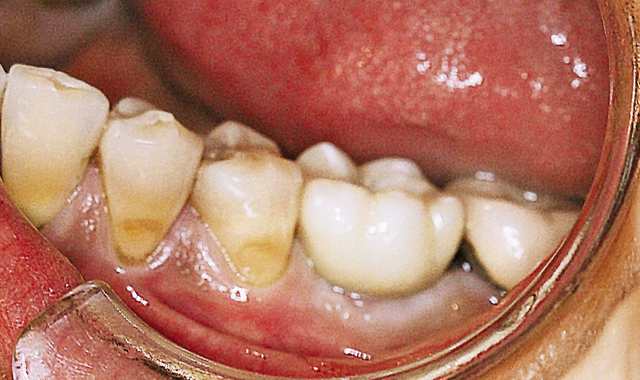

Six weeks later, an impression was taken (Fig. 9, above; Figs 10-12, below).

Fig. 10 After removing healing cap.